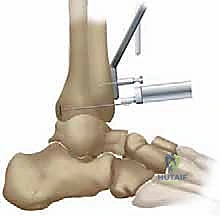

4. تجربة المفصل المؤقت (Trialing)

قبل تثبيت المفصل النهائي، يتم وضع مكونات بلاستيكية ومعدنية تجريبية. يقوم الدكتور هطيف بتحريك الكاحل في جميع الاتجاهات لاختبار نطاق الحركة، استقرار المفصل، وتوازن الأربطة. إذا لزم الأمر، يتم إجراء تعديلات طفيفة على العظام أو الأنسجة الرخوة.